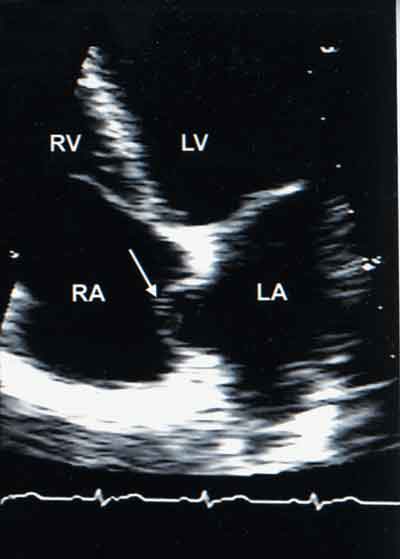

Interatrial septal aneurysms (IASA) and patent foramen ovale (PFO) (see previous image) frequently cause cryptogenic cerebral and peripheral thromboemboli. Recognition and documentation of these abnormalities during an echocardiographic study is essential. This view shows a typical IASA bulging into the right atrium in an asymptomatic 58-year-old man; there is no detectable PFO.

Image courtesy of Azam Ansari, MD and Ryan Devine, BS.